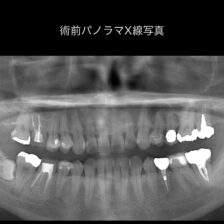

本当に根管治療が必要か?必要だとしてどの歯が原因なのか?

各種精密な診査を行い説明を行います。

また、根管治療によりどのくらいの成功率で残せるのか?

当院では世界的なエビデンスデータを用いながら当院オリジナルの治療実績も踏まえてご説明いたします。